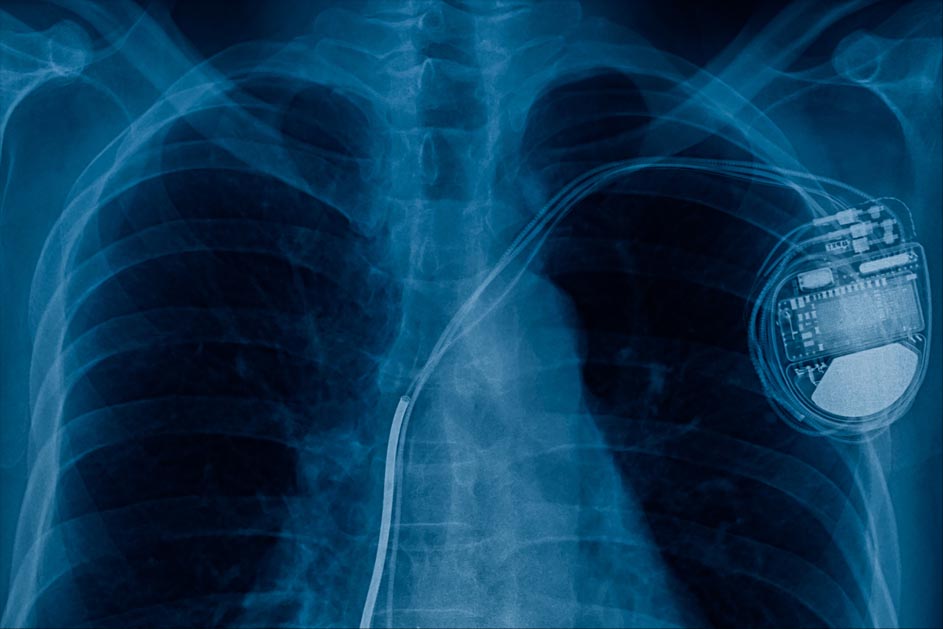

Cardiac implantable electronic devices (CIEDs), such as pacemakers and implantable defibrillators, save and extend lives. They are amazingly reliable and effective, but even the best tool comes with risks. As many as 1 in 20 patients with a CIED develops an infection within three years of implantation.

The science is clear about what to do: Patients with a CIED infection should be referred to a specialist with expertise in device extraction, and the CIED and all its components should be removed. This recommendation is supported by the American Heart Association, Heart Rhythm Society, British Heart Rhythm Society, European Society of Cardiology, and European Heart Rhythm Association. But despite the recommendations, many patients with CIED infection do not undergo complete system removal. Failure to remove the device is a life-or-death decision.